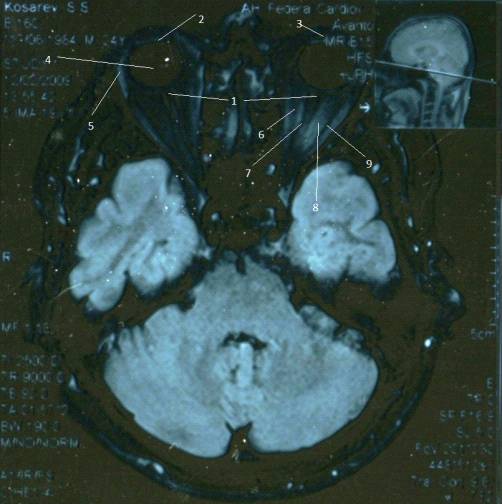

Проекция Мт №2

На Проекции Мт №2

визуализируются следующие

анатомические образования:

.Мышца поднимающая веко - M.Levator

palpebrae

.Наружняя прямая мышца - M.

Rectus externus

3.Нижняя

прямая

мышца

- M. Rectus inferior

.Общее

сухожильное

кольцо

- Annulus tendineus communis

.Глазное

яблоко

- Bulbus occuli

.Верхняя

косая

- M.obliquus superior

Проекция МТ №4

На Проекции Мт №4

визуализируются следующие анатомические

образования:

1.Верхняя

- M. Rectus superior

3.Латеральная прямая мышца - M.

Rectus lateralis

4.Нижняя

5.Медиальная прямая мышца - M.

Rectus medialis

.Слезоносовой канал Canalis

nasolacrimalis

. Твердая оболочка зрительного нерва

.Зрительный нерв - N.opticus

. Ретробульбарное пространство - Spatium

retrobulbar

.Блок - Trochlea